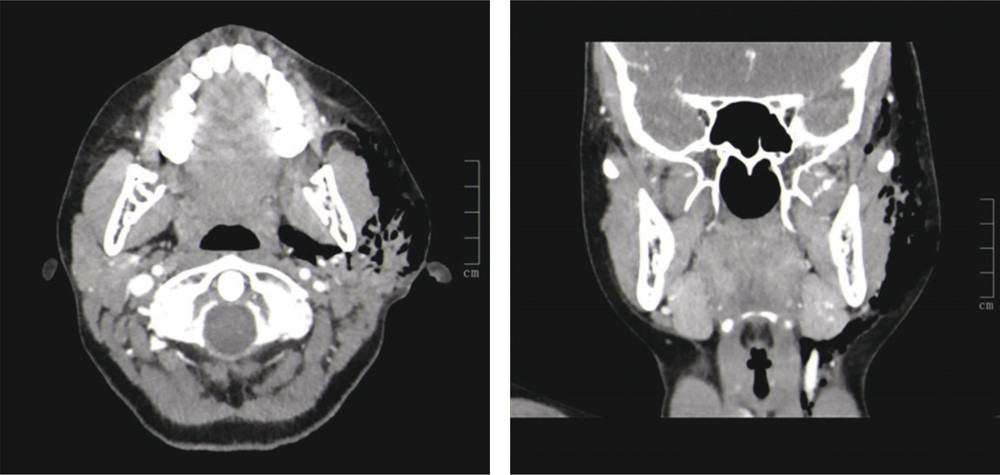

A CT scan with intravenous contrast was performed, since rapidly developing necrotising fasciitis was suspected due to the ultrasound finding. This showed pronounced emphysema throughout the left side of the face, but no sign of inflammation or abscess formation (photos – axial and coronal plane, air seen in black). The patient had increasing pain, swelling and redness the next day and was examined under anaesthetic with puncture, aspiration and probing of the parotid duct, without findings of anything pathological apart from air. This was amenable to aspiration, and the swelling was rapidly reduced. The girl spontaneously improved the following day and antibiotic treatment was discontinued. The condition was considered to be pneumoparotitis. She has since experienced several recurrences, from which she has spontaneously recovered.